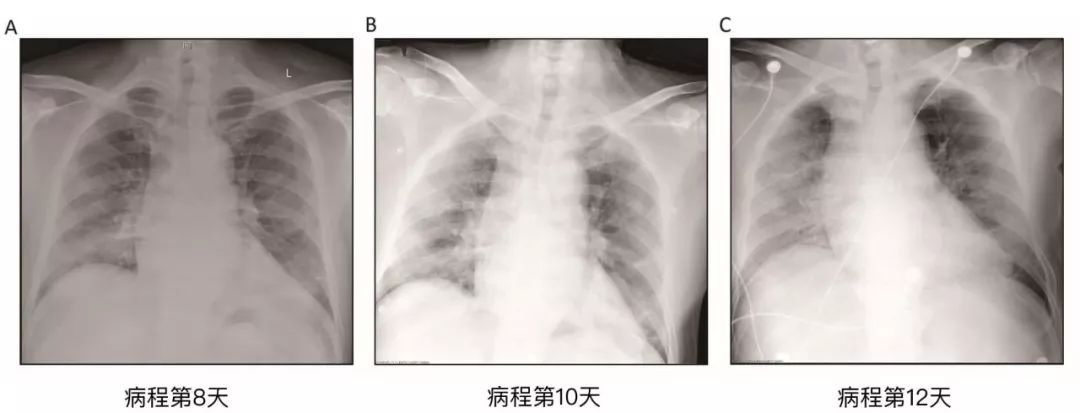

2020年1月21日,一名50岁的男子因发热、寒战、咳嗽、乏力和气促等症状被送往发热门诊。他报告了1月8日至12日的武汉旅行史,并且于1月14日(起病第1日)出现首发症状,表现为轻度寒战和干咳。但该患者仍继续工作,直到1月21日前往医院就诊(图1)。在医院对该患者进行了胸片检查并采集了咽拭子,胸片显示双肺多发性斑片影(附录p2)。1月22日(起病第9日),北京市疾病预防控制中心(CDC)通过qRT-PCR检测证实该患者为COVID-19。

在起病第12日,胸片显示患者双肺进行性浸润影和广泛网格状密度增高影。由于患者患有幽闭恐惧症,他多次拒绝ICU的呼吸机支持。因此,他接受了高流量鼻导管吸氧(HFNC),给氧浓度60%,流速40 L/min。在起病第13日,患者症状仍未改善,但血氧饱和度仍保持在95%以上。起病第14日下午,患者低氧血症和气促恶化。尽管接受了HFNC(给氧浓度100%,流速40 L/min),但血氧饱和度仍降至60%,并且患者突发心跳骤停。我们立即进行了有创通气、胸外按压和肾上腺素注射。但不幸未能复苏成功,该患者于北京时间1月27日18:31宣布死亡。

胸片图像提示肺炎迅速进展,双肺之间有些许差异。此外,肝组织表现出中度微血管脂肪样变性和轻度小叶活动性炎症,但是没有支持SARS-CoV-2病毒感染或者药物导致肝损伤的确切证据。心脏组织中未见明显的组织学变化,提示SARS-CoV-2感染可能不会直接损害心脏。